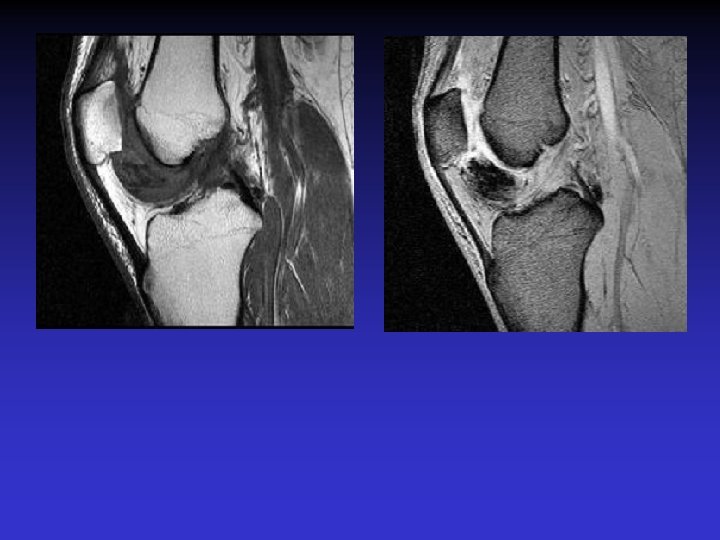

DIAGNOSTIC DIFFERENTIEL • Rupture du LCA • Tumeur synoviale

RUPTURE DU LCA

SVN